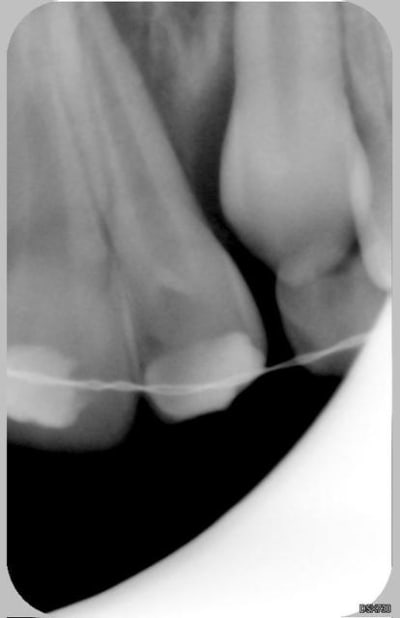

Patiente de 11 ans ayant la 21 expulsée début avril 2006. La dent a été repositionnée en centre de soins. Dans un premier temps, pas de perte de sensibilité. Puis dans un deuxième temps, comme un goût de ça tourne mal avec certainement rhyzalyse interne de la 22 (traitement thermafil pas d'école).

Ci joint la première radio de ces dents avec attelles centre de soins universitaire